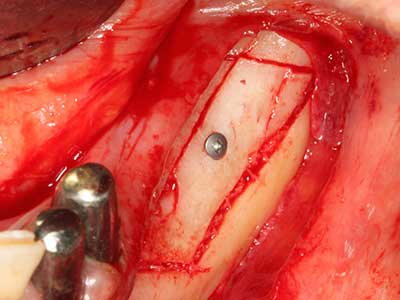

Si es preciso realizar intervenciones quirúrgicas en las que el hueso está en contacto directo con estructuras sensibles, como son los vasos sanguíneos o los nervios, los instrumentos rotativos presentan un enorme potencial de provocar lesiones iatrogénicas. Así, precisamente en la representación de nervios después de una lesión iatrogénica, o en el transcurso de la lateralización de un nervio para resecciones, reconstrucciones o incorporación de implantes, los equipos piezoeléctricos pueden resultar muy útiles para preparar la tapa ósea y retirar las partes de tejido duro cercanas al nervio (fig. 17-20). Por lo general, un ligero contacto del cordón nervioso con el inserto piezoeléctrico no tiene consecuencia alguna; ahora bien, un procedimiento poco cuidadoso con movimientos tipo sierra o piezas de trabajo sobre la base ósea aún existente puede provocar lesiones nerviosas temporales o incluso permanentes. Con todo, el riesgo de sufrir una lesión de este tipo se considera significativamente inferior que en los casos en los que se utilizan sierras y fresas (Pereira, Gealh et al. 2014).